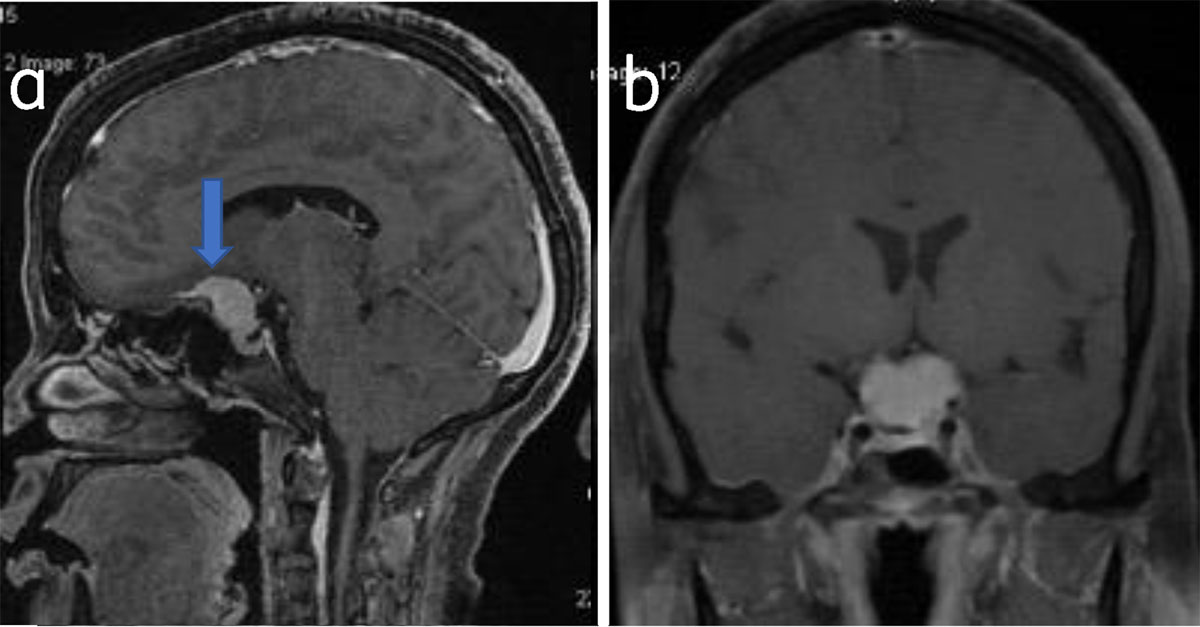

Figure 4

Suprasellar meningioma: Sagittal (a) and coronal (b) post-contrast T1W shows suprasellar meningioma (arrow).